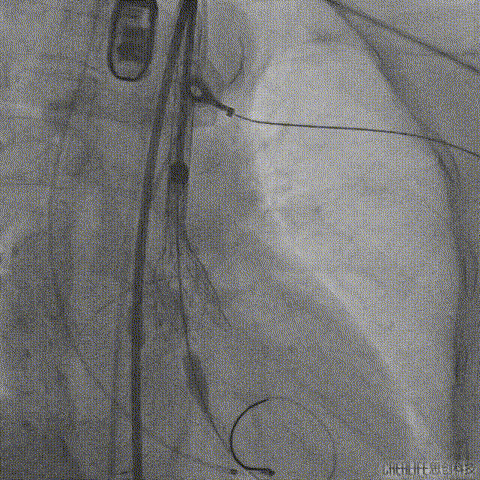

考虑到术中积极行冠脉保护,该手术从绕动脉穿刺造影指导左右股动脉穿刺;

经桡动脉穿刺造影指导左侧股动脉穿刺

经桡动脉穿刺造影指导右侧股动脉穿刺